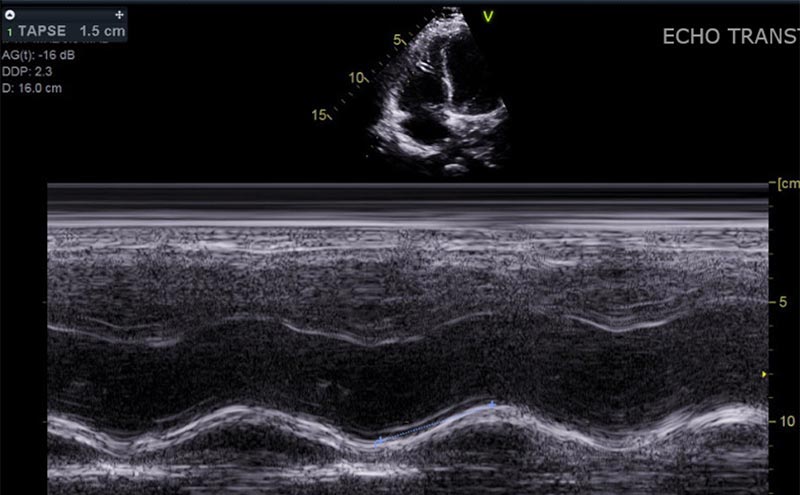

RV Strain

Description Here.